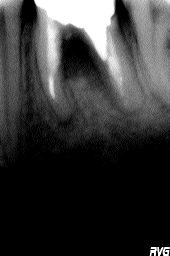

What are the implications of filling “short” in an Endodontic procedure? PART I

While this question could fill a small book, its answer has huge implications for the long-term success of endodontic therapy. In the most general terms, the greater the amount of uncleaned and unfilled canal space that remains after a root canal procedure, the greater failure rate. Conversely, if the endodontic procedure mimics extraction, the greater … Read more